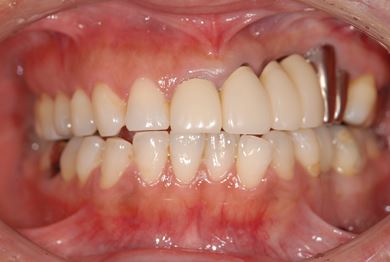

| 性別/年齢 | 女性 / 45歳 | ||||||||||||||||||||||||||||||||

| 主訴 | 以前治療した歯の歯ぐきから出膿。他の歯科でインプラントかブリッジしか方法がないが、骨の状態からインプラント治療は無理かもしれないと言われたことに不安を感じ、セカンドオピニオンを求めて来院。 | ||||||||||||||||||||||||||||||||

| 治療方針 | 保存不能の歯を抜歯し、インプラント治療にて機能的・審美的回復を行う。 | ||||||||||||||||||||||||||||||||

| 治療内容 | インプラント1本、ハイブリッドセラミッククラウン1本 | ||||||||||||||||||||||||||||||||

| 総治療費 | 310,905円 | ||||||||||||||||||||||||||||||||

| 治療期間 | 5ヶ月 |